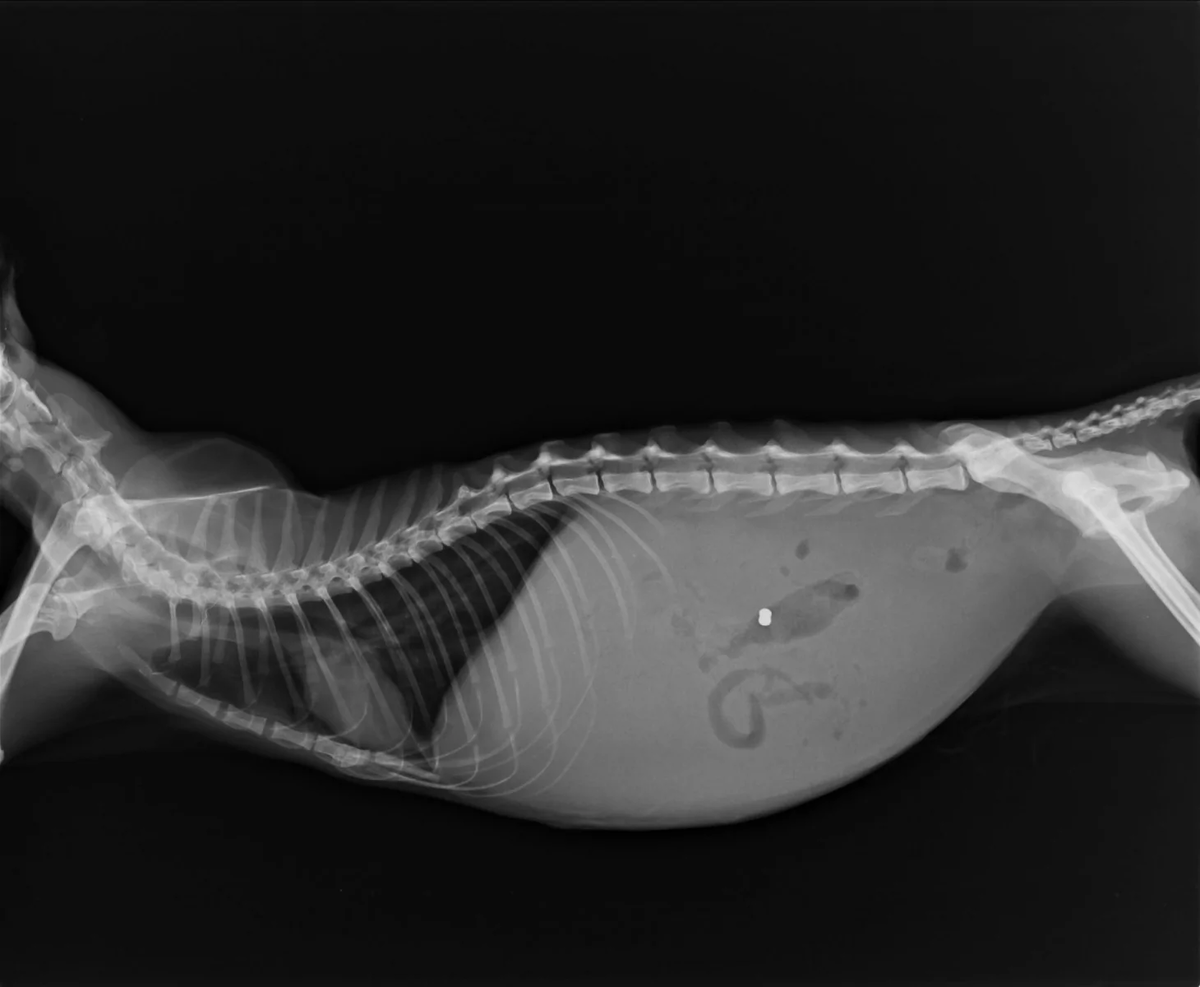

Скопление жидкости в брюшной полости у животных свидетельствует о серьезных изменениях в организме. Количество жидкости бывает разное и зависит от конкретного заболевания. Асцит, или иными словами выпот — это синдром, который возникает как осложнение в результате заболевания. Проявление асцита не ограничивается увеличением живота. В случае, когда собака или кошка стоит на лапах, форма живота приобретает форму груши. Прикосновения к животу вызывают неприятные, а в некоторых случаях болезненные ощущения. Среди других симптомов: Рентгенологический снимок, УЗИ, а также общий и биохимический анализы крови позволяют специалисту диагностировать асцит. Иногда для постановки диагноза необходима цитология. Выпот появляется вследствие заболеваний органов ЖКТ, печени, почек, сердца. Инфекции, опухоли и травмы также способны спровоцировать скопление жидкости в брюшной полости у животного. Влажная форма инфекционного перитонита кошек также характеризуется асцитом. ФИП — опасное заболевание, котор

Скопление жидкости в брюшной полости у животных свидетельствует о серьезных изменениях в организме. Количество жидкости бывает разное и зависит от конкретного заболевания.

Асцит, или иными словами выпот — это синдром, который возникает как осложнение в результате заболевания.

Проявление асцита не ограничивается увеличением живота. В случае, когда собака или кошка стоит на лапах, форма живота приобретает форму груши. Прикосновения к животу вызывают неприятные, а в некоторых случаях болезненные ощущения.

Рентгенологический снимок, УЗИ, а также общий и биохимический анализы крови позволяют специалисту диагностировать асцит. Иногда для постановки диагноза необходима цитология.